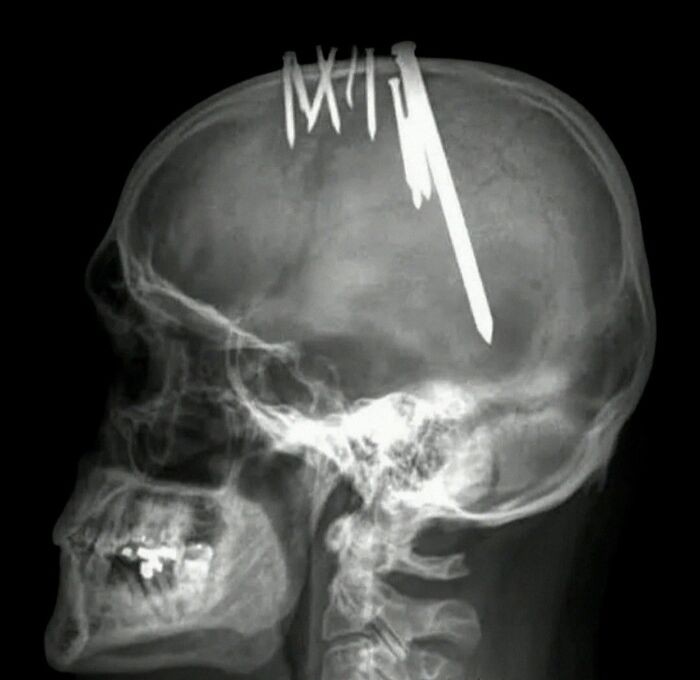

Seorang pria berusia 44 tahun datang ke unit gawat darurat mengenakan topi baseball dan mengeluh sakit kepala hebat yang semakin memburuk selama 11 minggu sebelumnya. Ketika pasien melepas topinya, terungkap bahwa berbagai benda logam tertanam di kulit kepalanya. Foto: Boredpanda